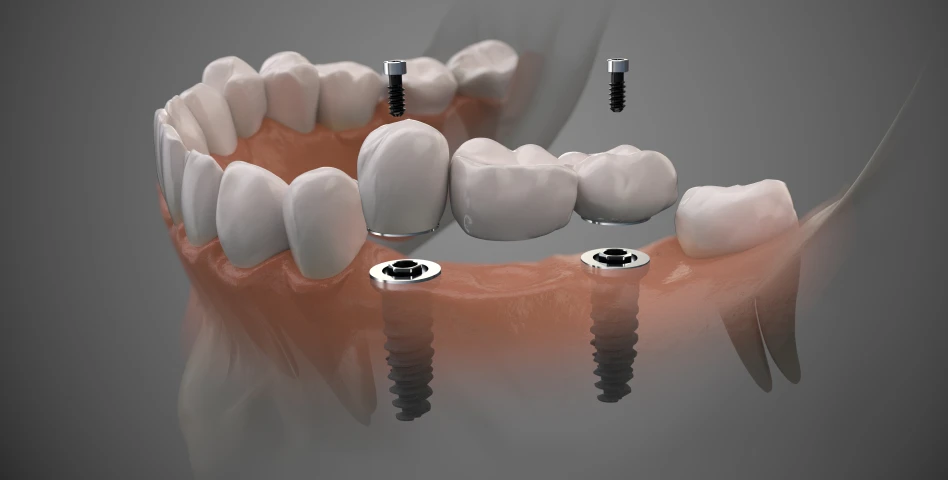

C’est une racine artificielle en titane placée dans l’os de la mâchoire pour remplacer une dent manquante.

C’est une racine artificielle en titane placée dans l’os de la mâchoire pour remplacer une dent manquante.